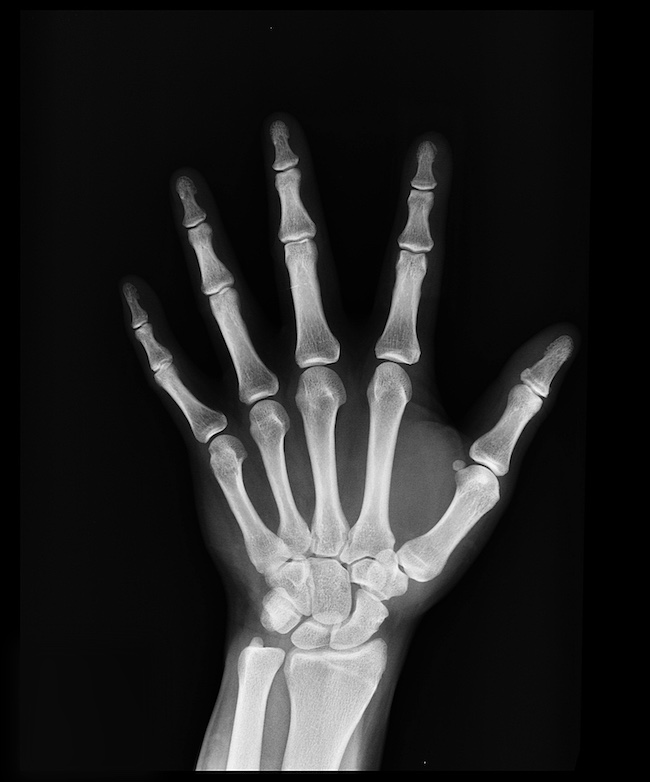

Anotación ósea y esquelética

Contornos óseos y segmentación estructural

Etiquetamos los contornos óseos, las áreas articulares, las regiones de fracturas y los puntos de referencia ortopédicos en las radiografías del esqueleto.